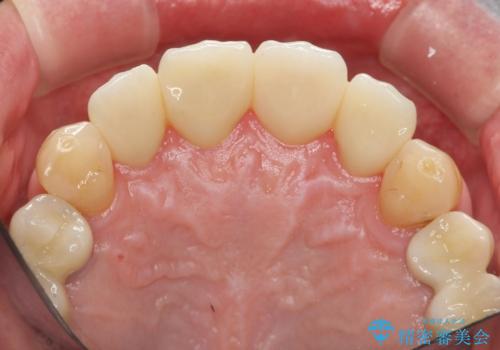

「 放置した虫歯 」 前歯セラミック治療

- 61.6万円(仮歯・ジルコニアクラウン×4・ファイバーコア ・エクストリュージョン)費用は治療当時の料金となります

虫歯の放置により、根管治療や深い虫歯に対する処置が必要になりましたが丁寧に一つづつ処置を行ったことで抜歯をすることなく歯を残すことができました。

セラミッククラウンの製作をする前に、歯内・歯周環境の整備は非常に大切です。